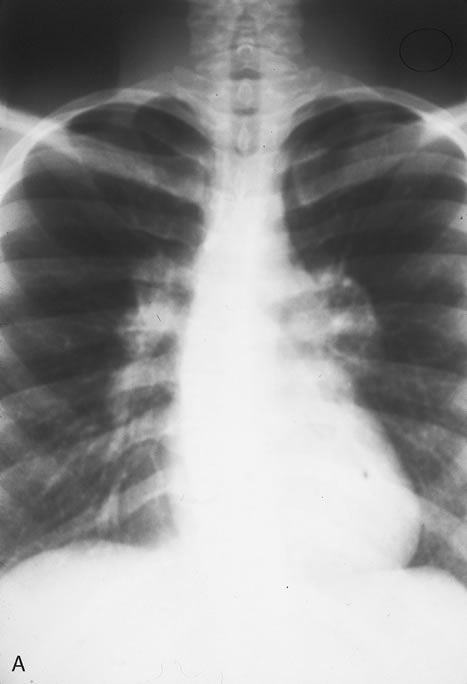

Therapy for genital chlamydia infection is administration of tetracycline, doxycycline, or erythromycin for 2 to 3 weeks. Asymptomatic sexual contacts should be treated as they are likely to harbor genital chlamydial infections. Treatment failures are rare. The recommendation has been made to test conjunctival scrapings three weeks following completion of the course of antibiotics as some patients may require two to three courses of antibiotic therapy.59 TUBERCULOSIS Mycobacterium tuberculosis is a bacterium that causes infection through inhalation of aerosolized droplets filled with the organism. An asymptomatic pulmonary granuloma may develop and reactivate at any point, particularly when accompanied by diseases such as HIV, malignancy, and diabetes mellitus. Rates of reactivity have been found to be highest in non-white, older men of lower socioeconomic status. In the last decade a resurgence of tuberculosis (TB), particularly in crowded urban settings such as New York City, has been noted.60 Ocular involvement most commonly occurs after reactivation in the lung or alimentary tract and is thus referred to as secondary TB (Fig. 16). Primary ocular involvement of TB is rare and is almost always limited to the cornea and conjunctiva. Conjunctival TB has been reported as a chronic unilateral conjunctivitis with a conjunctival mass or ulceration associated with regional lymphadenopathy. Although also rarely seen, conjunctival phlyctenulosis has been found to be associated with tuberculoprotein hypersensitivity. Biopsy and culture proven scleral TB was reported in the literature in 1976 and 1989. Other ocular manifestations of TB include anterior uveitis, either granulomatous or nongranulomatous, choroiditis, and choriodal tubercles/tuberculoma. A recent case series demonstrated the protean ocular findings associated with intraocular TB in addition to a variable response to antitubercular treatment.61

The gold standard for diagnosis of intraocular tuberculosis is demonstration of acid-fast bacilli in fluid or tissue sample either by direct smear and culture, polymerase chain reaction (PCR) or ELISA (Fig. 17). A screening test such as the Mantoux test is useful but is less specific and must be interpreted based on the size of induration in correlation with socioeconomic status, immune status, and contact history of the patient. The test consists of an intradermal injection of purified protein derivative (PPD) from tubercle bacilli. Systemic sensitization to this protein occurs several weeks after primary infection. At 48 to 72 hours postinjection, skin induration larger than 5 mm in an HIV-positive patient or patients with a positive chest x-ray that are previously untreated, larger than 10 mm in other high-risk populations, and larger than 15 mm for healthy patients with low risk factors are considered significant. A positive reaction may persist in the absence of clinically active disease and therefore must be correlated with chest radiography and symptomatology.